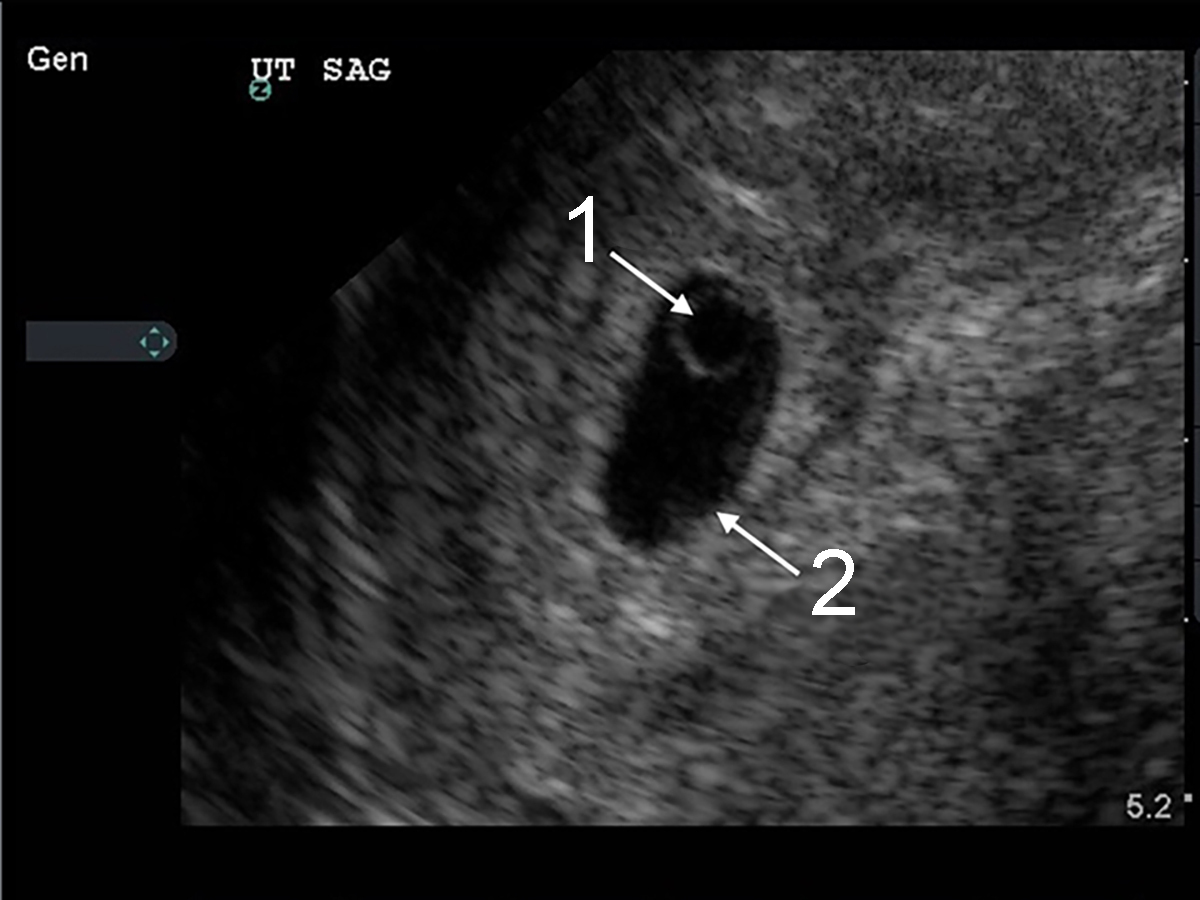

Bild 1: Transvaginaler (TV) Ultraschall des Beckens, Intrauteringravidität mit Dottersack, Zoom

1. Dottersack

2. Gestationssack